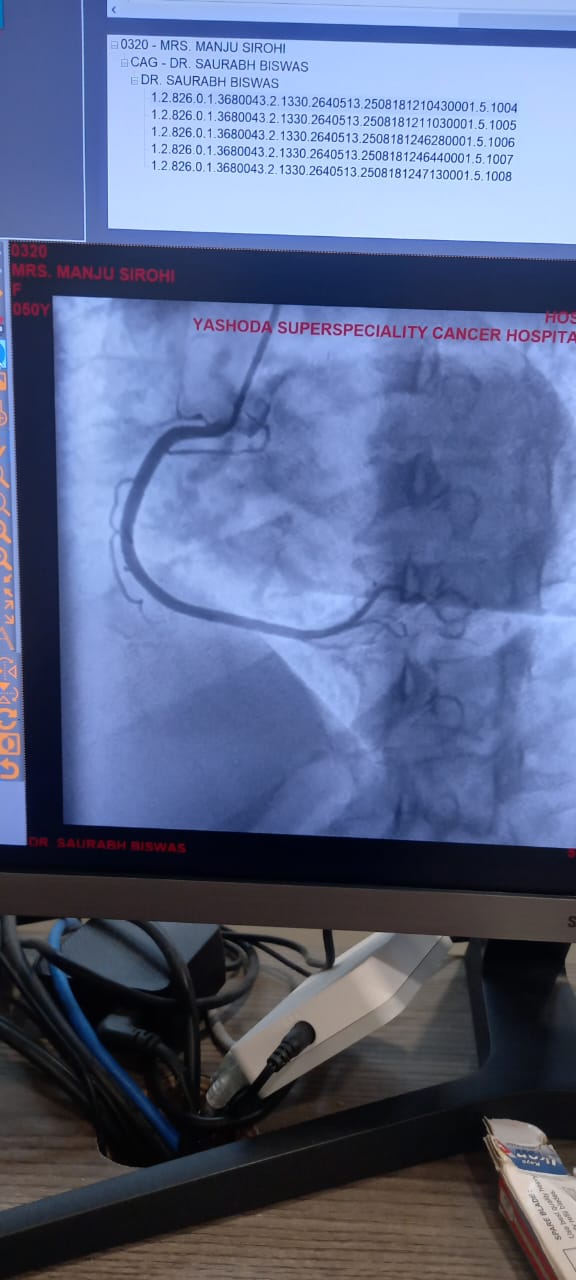

Angiography / Cardiac Cath

Angiography, also known as Cardiac Catheterization, is a minimally invasive procedure used to diagnose heart conditions. It provides detailed images of the heart's blood vessels, helping doctors detect blockages or narrowing.

Once it reaches the heart, a contrast dye is injected. The dye makes the coronary arteries visible on an X-ray screen, revealing any blockages, plaque buildup, or structural issues.

• Coronary Angiography: This is the most common type. It evaluates the coronary arteries for blockages or narrowing.